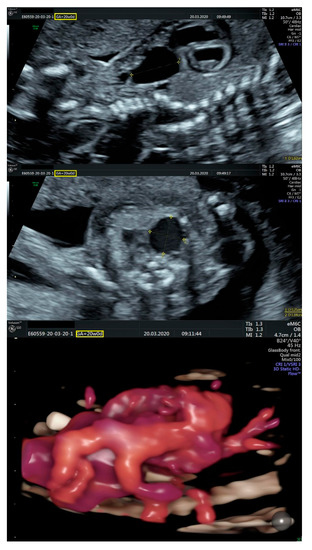

2.1. Ultrasound Findings

- an isolated aortic arch anomaly (supposedly aneurysmal dilation from which the left common carotid artery emerges) and coarctation of the aorta with the anterograde flow;

- ventricular septal defect, coarctation of the aorta, and a vascular formation located superior from the aortic arch with the appearance of an arteriovenous fistula;

- aneurysmal dilation located above the pulmonary trunk bifurcation and a dilated left common carotid artery with a retrograde flow;

- minor ventricular septal defect with a normal ductus venosus triphasic flow.